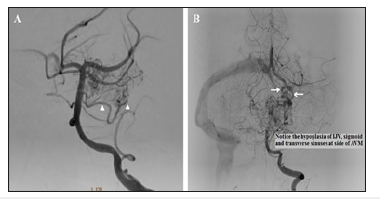

Diagnostic angiogram was done and showed a cisternal AVM that has the following angioarchitecture criteria:

A. Nidal size: 3,5cmx2.4cm with 2 initial venous compartments.

B. Arterial feeder: multiple large pontine perforators arising from the most proximal long circumferential branch and many short circumferential branches.

C. Draining veins: Two venous tributaries draining into the left basal vein of Rosenthal; the most tortuous is the lateral mesencephalic vein (Figure 2).

Figure 2:Diagnostic angiography: AP left vertebral arteriogram. (A) Arterial phase: showing multiple pontine perforators feeding the AVM; arising mainly from the most proximal long circumflex branch. (B) Early venous phase: showing two draining veins; the most tortuous of them is the lateral mesencephalic vein. Both of them are drained by the left basal vein of Rosenthal.